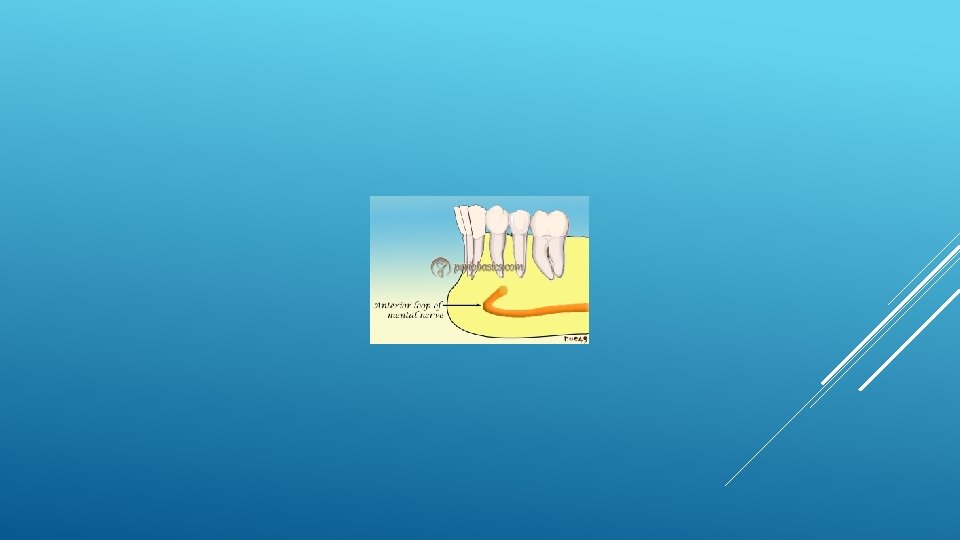

LOCATION AND DIMENSIONS OF THE MENTAL FORAMEN: A RADIOGRAPHIC ANALYSIS BY USING CONE-BEAM COMPUTED TOMOGRAPHY The majority of MF (56%) were located apically between the 2 premolars, and another 35. 7% of MF were positioned below the second premolar. On average, the MF was localized 5. 0 mm from the closest root of the adjacent tooth (range, 0. 3 -9. 8 mm). The mean size of the MF showed a height of 3. 0 mm and a length of 3. 2 mm; however, individual cases showed large differences in height (1. 8 -5. 1 mm) and in length (1. 8 -5. 5 mm). All mental canals exiting the MF demonstrated an upward course in the coronal plane, with 70. 1% of the mental canal presenting an anterior loop (AL) in the axial view. The mean extension of AL in cases with an AL was 2. 3 mm.

THE MENTAL FORAMEN OR "THE CROSSROADS OF THE MANDIBLE. " AN ANATOMIC AND CLINICAL OBSERVATION] [ARTICLE IN FRENCH, GERMAN] THOMAS VON ARX 1 This paper presents a clinical and anatomical review of the mental foramen (MF) based on recent publications (since 1990). Usually, the MF is located below the 2 nd premolar or between the two premolars, but it may also be positioned below the 1 st premolar or below the mesial root of the 1 st molar. At the level of the MF, lingual canals may join the mandibular canal (hence the term "crossroads"). Accessory MF are frequently described in the literature with large ethnic variations in incidence. The emergence pattern of the mental canal usually has an upward and posterior direction. The presence and extent of an "anterior loop" of the mental canal may be overestimated with panoramic radiography. Limited cone-beam computed tomography currently appears to be the most precise radiographic technique for assessment of the "anterior loop". The mental nerve exiting the MF usually has three to four branches for innervation of the soft tissues of the chin, lower lip, facial gingiva and mucosa in the anterior mandible. The clinician is advised to observe a safety distance when performing incisions and osteotomies in the vicinity of the MF.

ANATOMICAL RELATIONSHIP BETWEEN MENTAL FORAMEN, MANDIBULAR TEETH AND RISK OF NERVE INJURY WITH ENDODONTIC TREATMENT he root apex of the mandibular second premolar (70 %), followed by the first premolar (18 %) and then the first molar (12 %), was the closest to the MF. Ninetysix percent of root apices evaluated were >3 mm from the MF. An AL was present in 88 % of the cases. Conclusions: With regards to endodontic treatment, the risk of nerve injury in the vicinity of the MF would appear to be low. However, the high incidence of the AL highlights the need for clinicians to be aware and careful of this important anatomical feature.